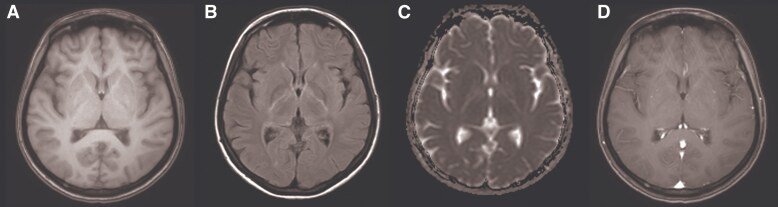

眼阵挛-肌阵挛-共济失调综合征(OMAS)是一种罕见的神经免疫疾病,病因多样,包括感染相关的触发因素,如人类免疫缺陷病毒(HIV)感染。在此,我们报告一例hiv相关的OMAS在抗逆转录病毒治疗(ART)-naïve患者谁提出脑脊液(CSF)/血浆HIV-1 RNA不一致。一名16岁的女性在OMAS发病后被诊断为HIV。脑脊液HIV-1 RNA水平高于血浆。抗逆转录病毒治疗开始后,脑脊液HIV病毒载量和OMAS症状同时改善。该病例表明CSF/血浆HIV-1 RNA不一致可发生在ART-naïve hiv相关OMAS患者中。此外,我们的研究结果表明,在这种情况下,仅通过ART进行病毒抑制可能足以实现临床解决,而无需辅助免疫抑制治疗。

Opsoclonus-myoclonus-ataxia syndrome (OMAS) is a rare neuroimmunological disorder with diverse etiologies, including infection-associated triggers such as human immunodeficiency virus (HIV) infection. Herein, we report a case of HIV-associated OMAS in an antiretroviral therapy (ART)-naïve patient who presented with cerebrospinal fluid (CSF)/plasma HIV-1 RNA discordance. A 16-year-old female was diagnosed with HIV following the onset of OMAS. The CSF HIV-1 RNA level was higher than that in the plasma. After ART initiation, both the CSF HIV viral load and OMAS symptoms improved simultaneously. This case demonstrates that CSF/plasma HIV-1 RNA discordance can occur in ART-naïve patients with HIV-associated OMAS. Moreover, our findings suggest that, in such cases, viral suppression through ART alone may be sufficient to achieve clinical resolution without the need for adjunctive immunosuppressive therapy.